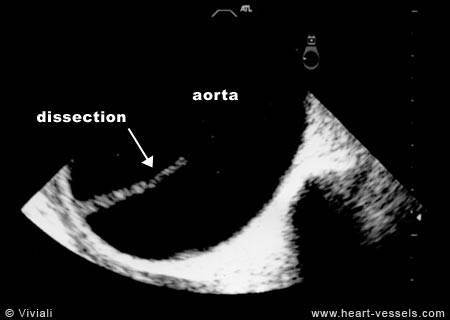

Aortic Dissection